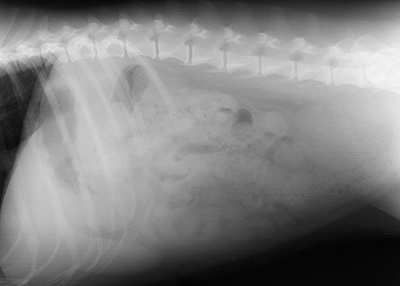

Radiograph of the Right lateral view

Figure 1: Right lateral view